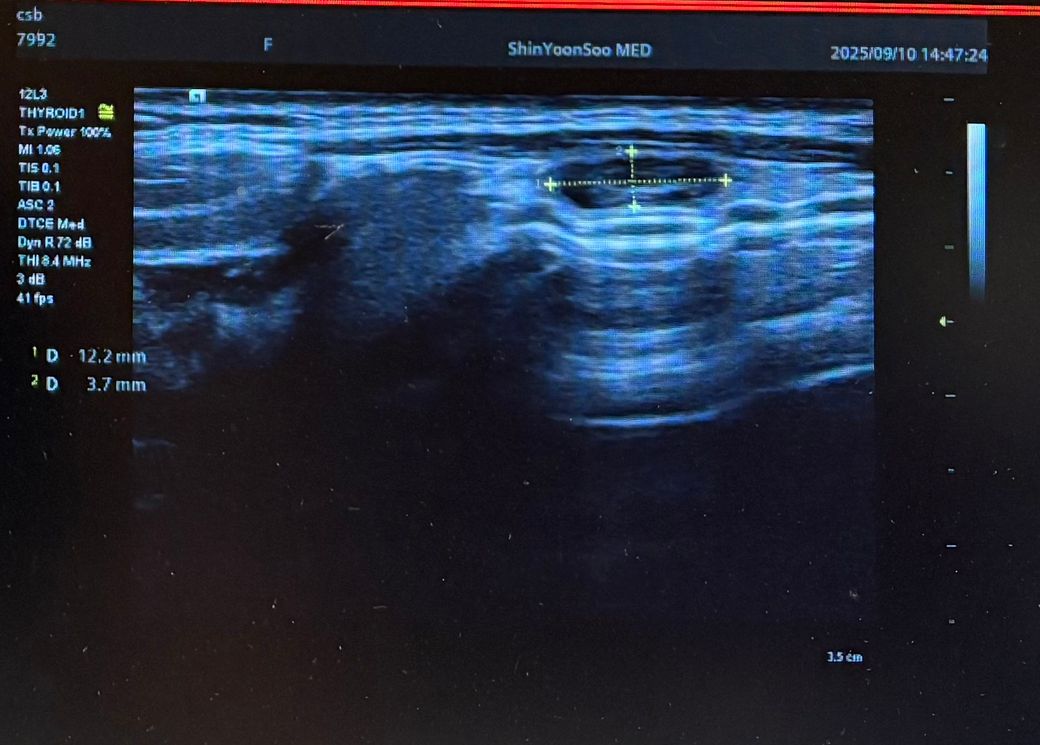

최근 동네 의원에서 갑상선초음파를 보다가 왼쪽 갑상선에 큰 혹 한개와 작은혹 한개가 발견되어 조직검사가 필요할것 같다고 의뢰서를 써주셔서 상급병원으로 예약잡고 저번주에 초진 봤습니다.

Lt 1ower lobe

1.88x1.4x2.84cm mixed nodule Lt middle lobe 1.22x0.37x 0. 49cm의 nodule 소견으로(의뢰서에 적혀있던 내용) 초진 보러가니 초음파 사진만 보시고는 식도와 신경에 들러붙어있고 점점점 커지면서 추후엔 응급수술로 진행될 수 있으니 아직 젊을때 빠르게 수술로 떼어내자고 결론은 수술밖에 없다고 냅다 수술일정 한달뒤로 잡고왔습니다.

왼쪽에 약 3cm가량으로 전체가 혹일거라며 상황이 많이 안좋은거고 위치가 안좋다고 하셔서 다음주에 수술전 검사 받은 후 2주뒤 입원으로 일정이 잡혔는데 보통 세침검사 또는 총생검사 후 수술 여부가 결정되는걸로 알고있는데 ..

• 3번 째 사진